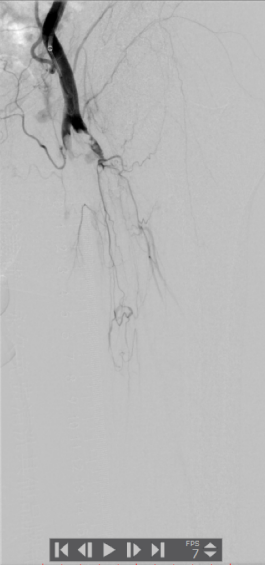

1.穿刺右侧股总动脉,“翻山”至对侧股总动脉,造影:股浅、股深动脉、腘动脉完全闭塞,膝下可见少量侧支动脉代偿。

▲患者术中即时造影显示股浅、股深动脉完全栓塞

▲腘动脉可见充盈缺损

▲膝下主干动脉未见显影